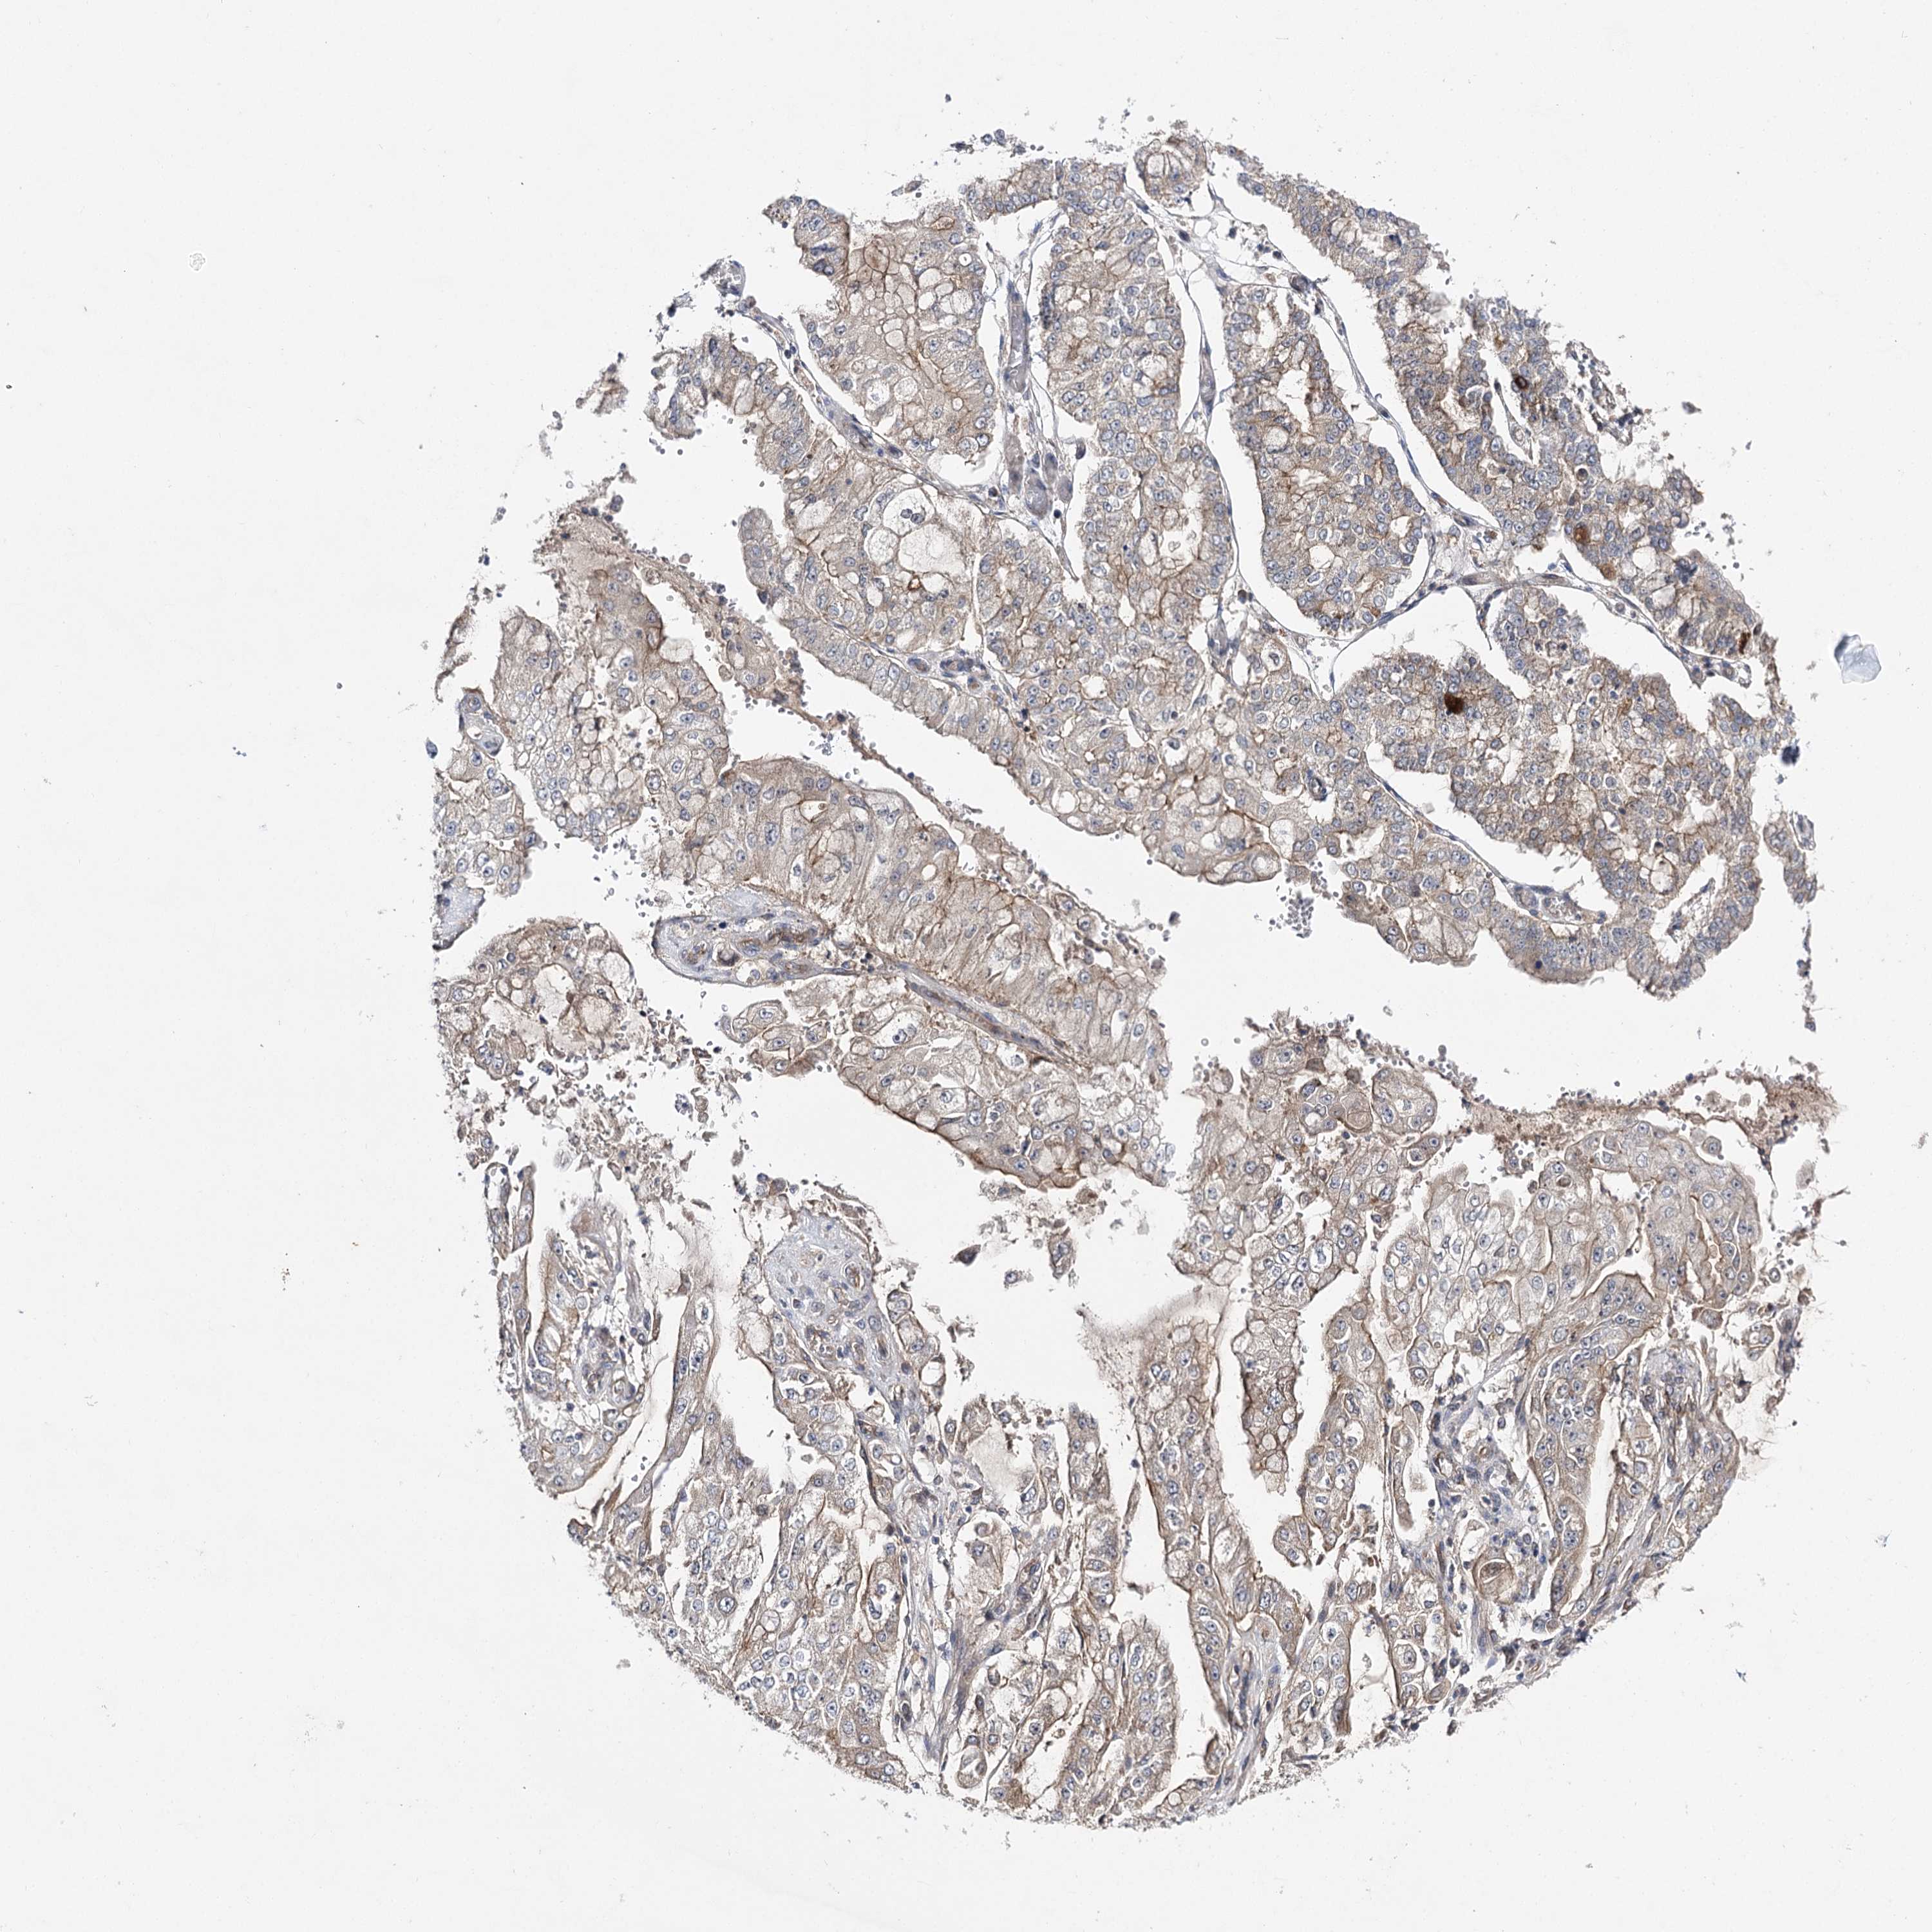

STOMACH CANCER - Protein expressioni

A mouse-over function shows sample information and annotation data. Click on an image to view it in a full screen mode. Samples can be filtered based on level of antibody staining by selecting one or several of the following categories: high, medium, low and not detected. The assay and annotation is described here.

Note that samples used for immunohistochemistry by the Human Protein Atlas do not correspond to samples in the TCGA dataset.

Antibody stainingi

Antibody staining in the annotated cell types in the current human tissue is reported as not detected, low, medium, or high, based on conventional immunohistochemistry profiling in selected tissues. This score is based on the combination of the staining intensity and fraction of stained cells.

Each image is clickable and will lead to virtual microscopy that enables deeper exploration of all samples and also displays staining intensity scores, fraction scores and subcellular localization as well as patient and tissue information for each sample.

Antibody HPA038337

Antibody CAB010421

Antibody CAB018545

Staining

High

Medium

Low

Not detected

Intensity

Strong

Moderate

Weak

Negative

Quantity

>75%

75%-25%

<25%

None

Location

Nuclear

Cytoplasmic/membranous

Cytoplasmic/membranous,nuclear

Adenocarcinoma, NOS